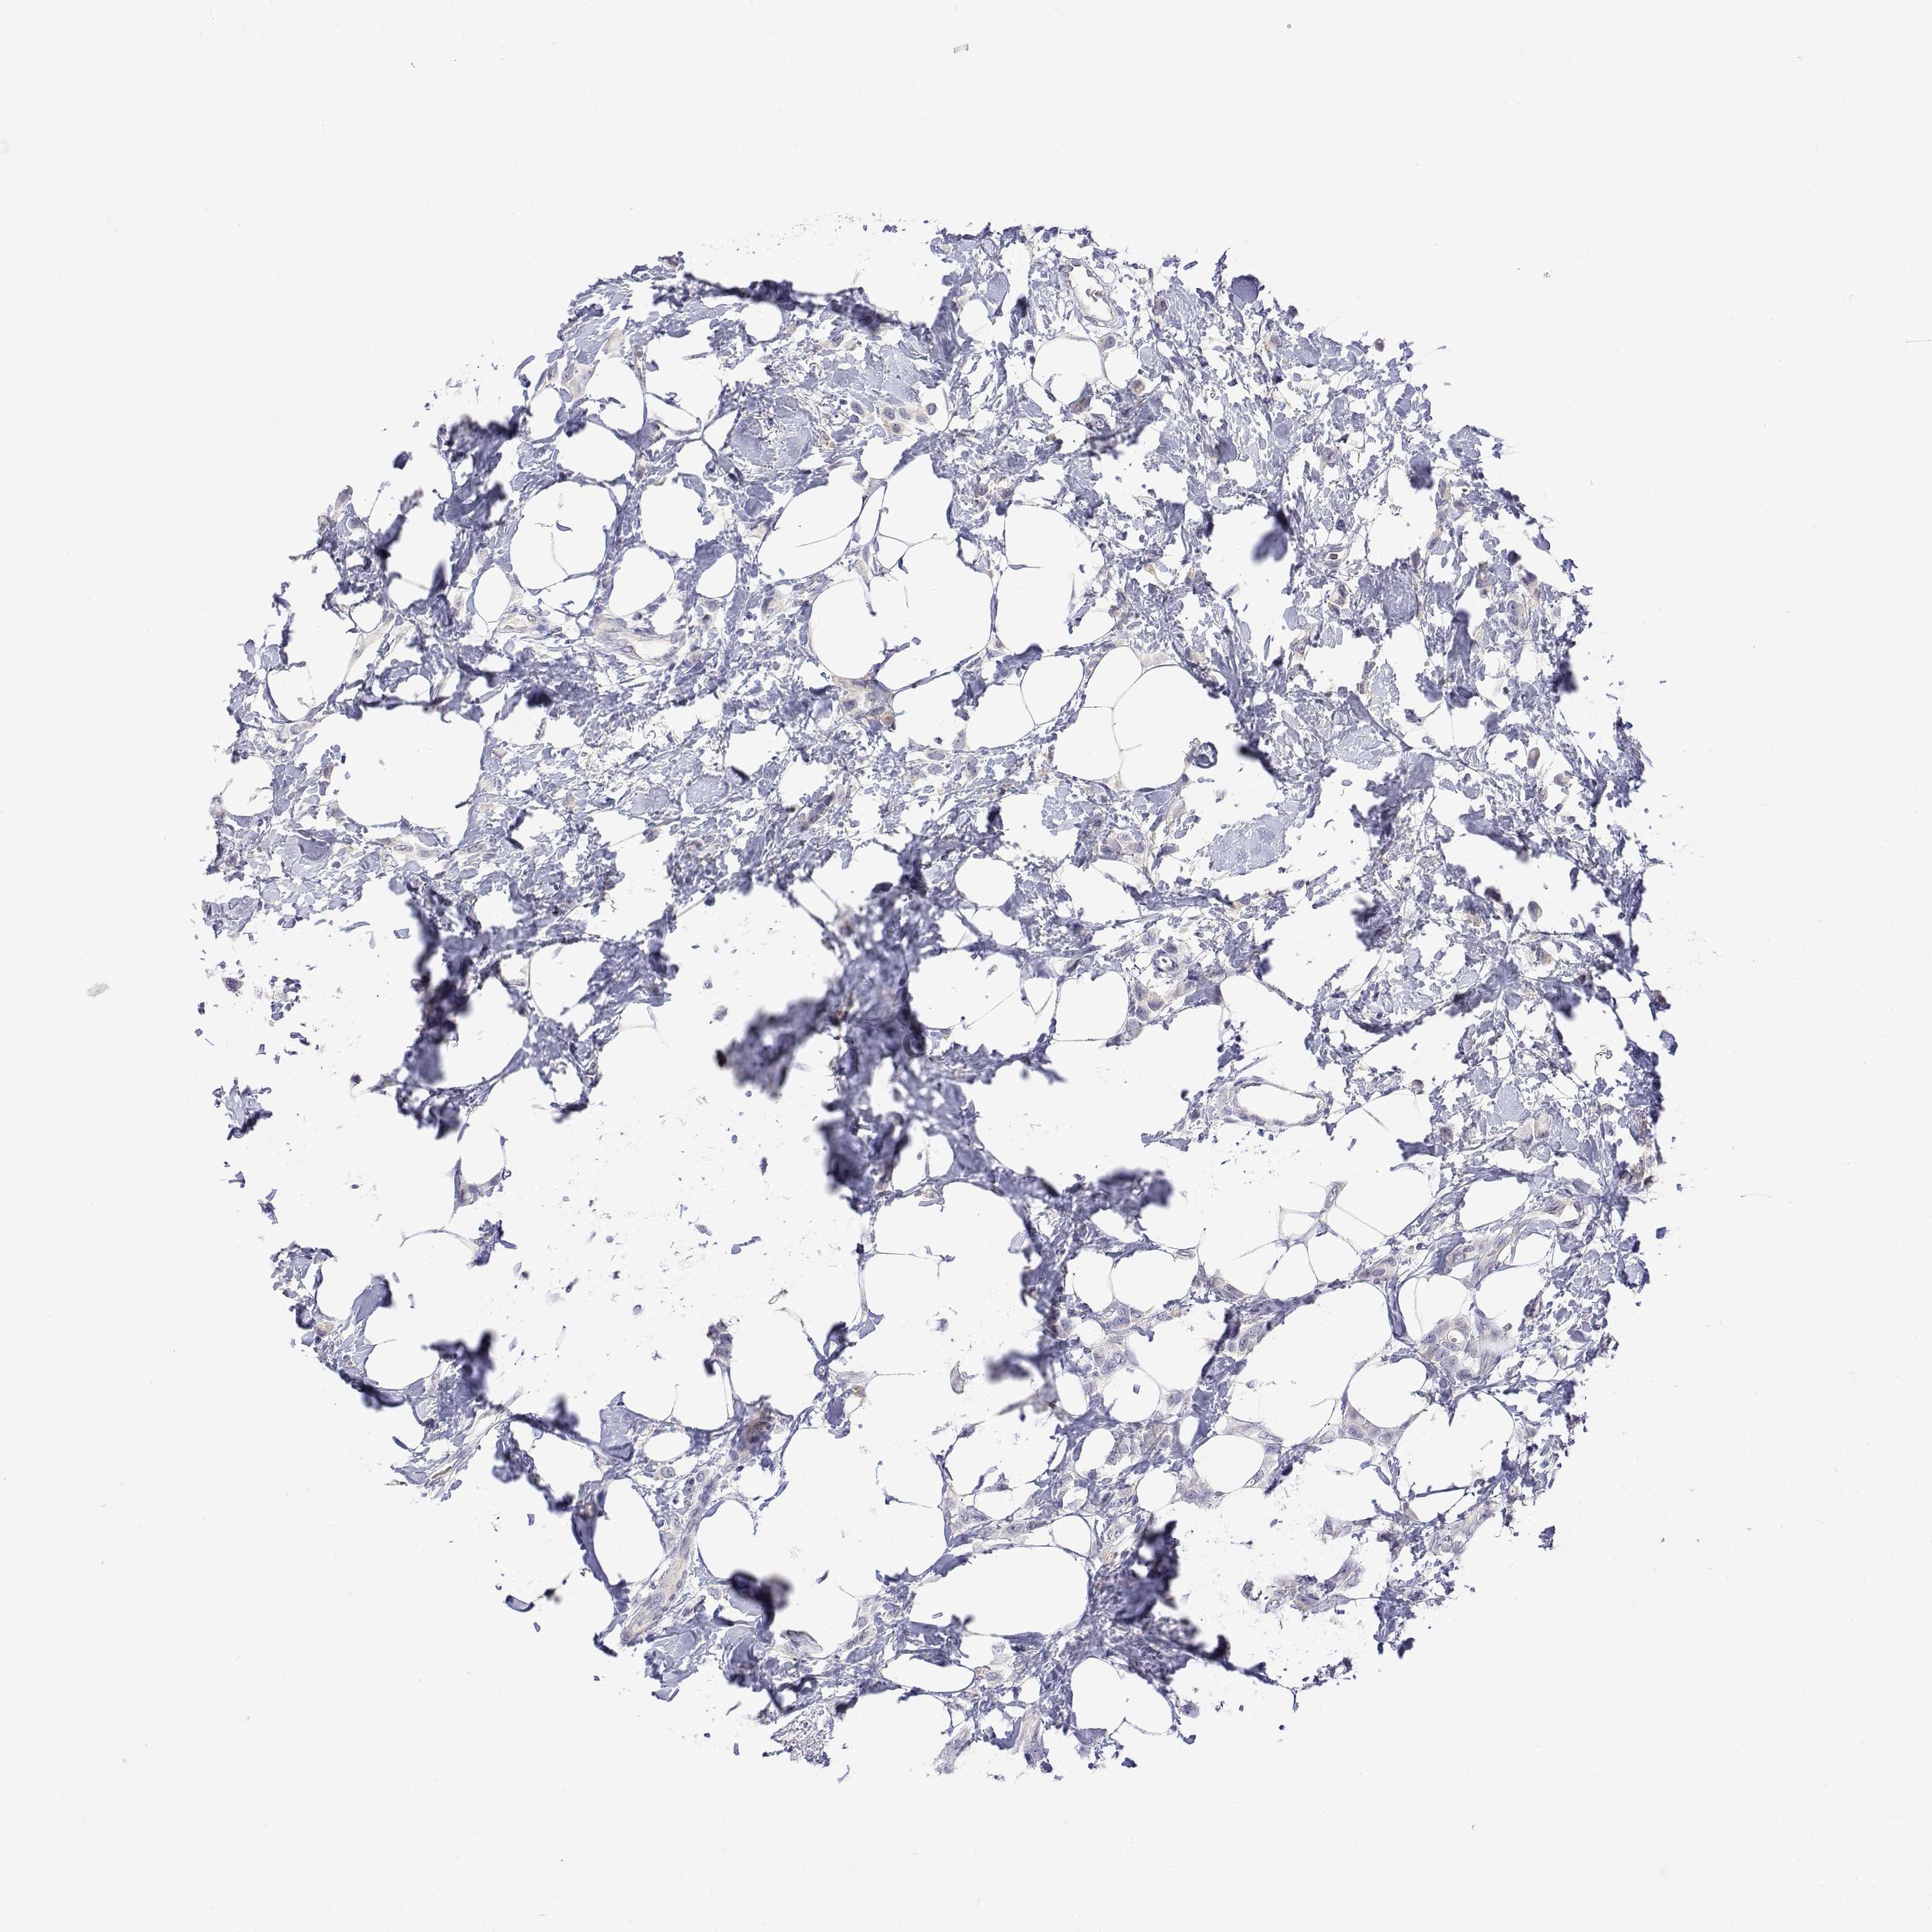

CANCER BREAST CANCER Show tissue menu

BRCA TCGA BRCA VALIDATION PROTEIN EXPRESSION

Breast cancer

Human cancer